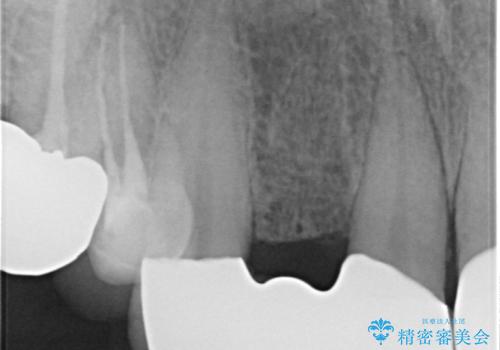

また、左上の犬歯の根の再治療も行いました。

- ジルコニアクラウンスタンダード・仮歯 13.2万円×6 左上3精密根管治療(リトリートメント)・ファイバーコア 12.1万円費用は治療当時の料金となります